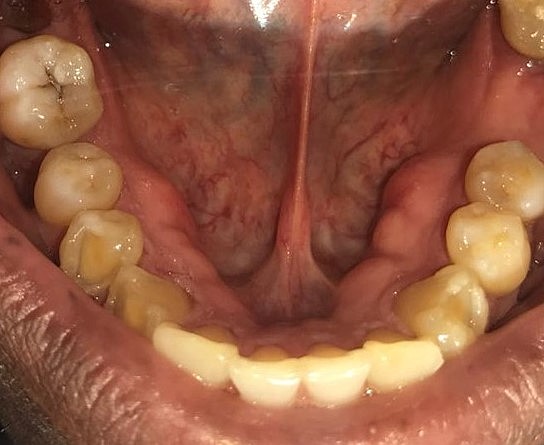

• Fotografías intra orales

Fotografías intra orales

Se tomaron fotografías para tener un registro durante el tratamiento.

Se realizará cirugía del torus lingual, para poder confeccionar la prótesis parcial removible.